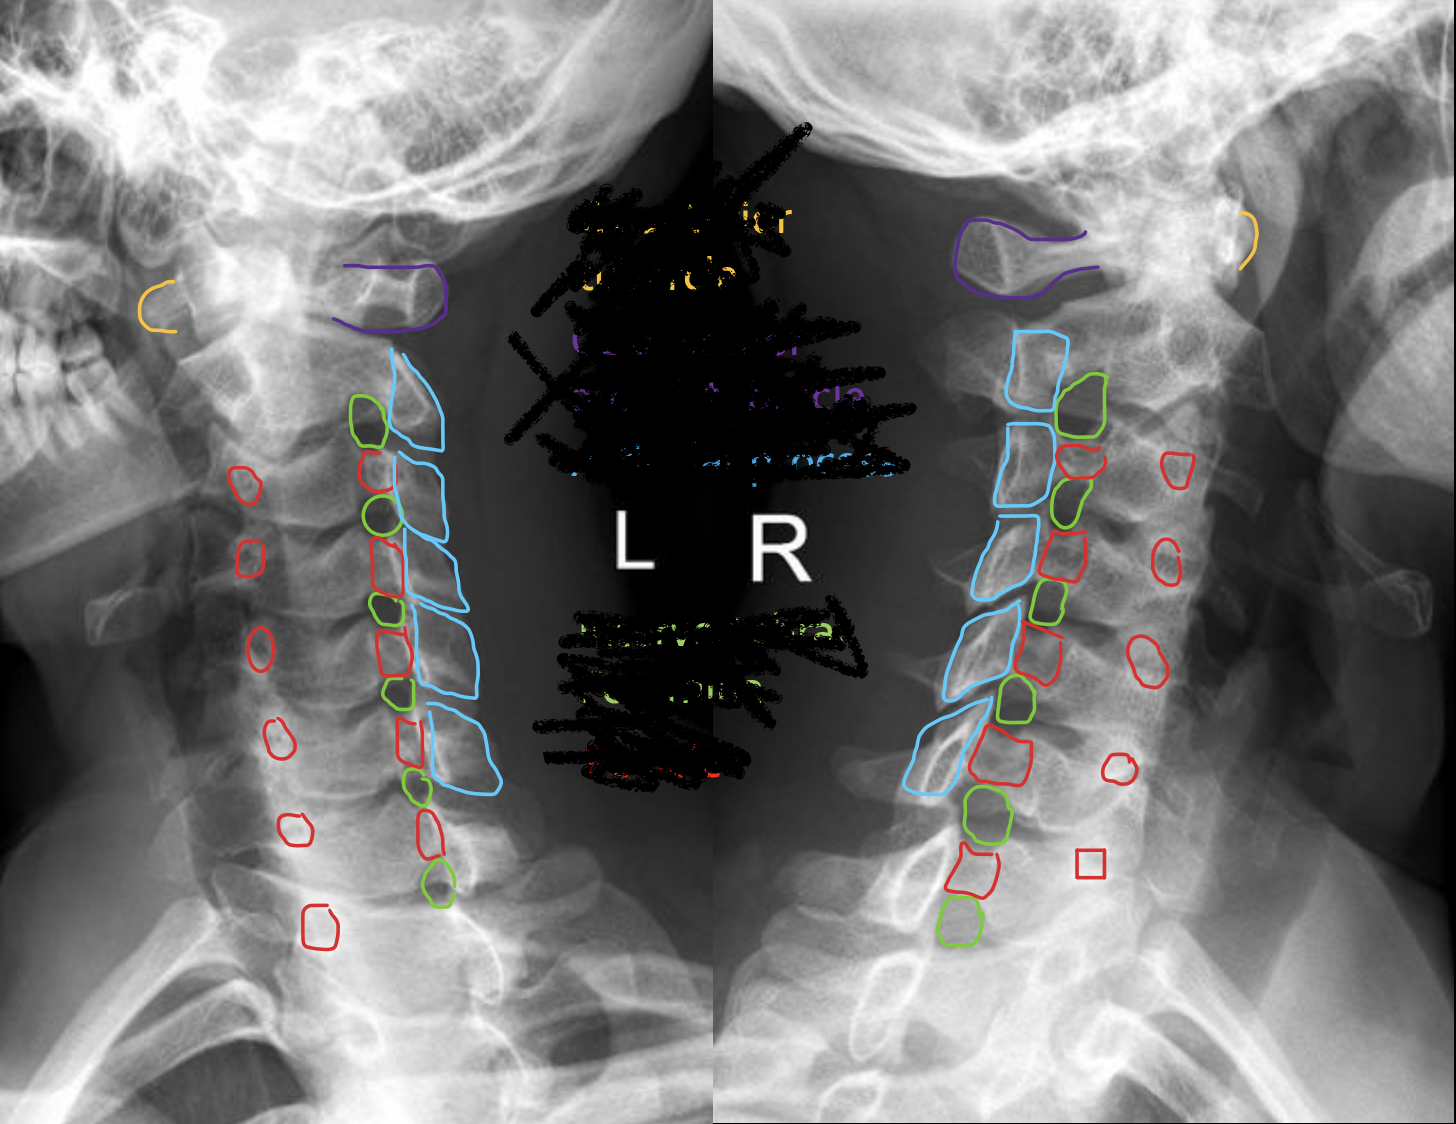

C2

C3

C4

c5

c6

c7

T1

1ST Rib

钩突

Uncinate process

关节柱 / 侧块

Articular pillars

棘突

Spinous process

乳突气房

Mastoid air cells

下颌角

Angle of mandible

椎间隙(Intervertebral Disc space)

IVD space

气管

Trachea

齿状突

Odontoid process C1